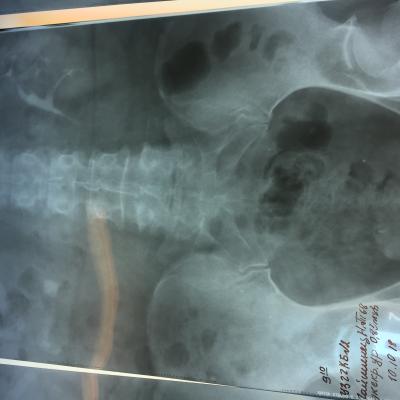

Камень в почках размер 25 мм

Беспокоила тяжесть в почке и периодические боли, часто выходили мелкие камни, после очередного приступа обратилась к врачу и попала в Больницу, сделали снимки ( фото прилагается) обнаружен крупный камень размером 25 мм и несколько мелких . Что делать? Не знаю? Дайте пожалуйста рекомендации!!! Удалять камень? Каким способом операция либо новыми технологиями это возможно?